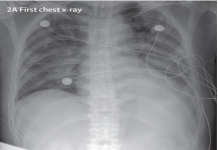

This dataset is formed by taking 25 images of COVID-19 from [35] in the first step. We then add another 75 non-Covid cases of chest X-ray image from [36]. It is important to note that these non-Covid (normal) cases might consist of other unhealthy conditions such as bacterial or viral infections, chronic obstructive pulmonary disease and even a combination of two or more. Accordingly, what we mean by a normal or non-Covid case does not necessarily infer a healthy lower respiratory system. Two images of covid and normal classes are shown in Fig. 2. Fig. 2(b) displays a normal (non- Covid) case, yet virally infected. All images in this dataset are accessible via this link: https://github.com/dara1400/Covid19-Xray-Dataset.

Figure 2: Two sample images from X-ray dataset.